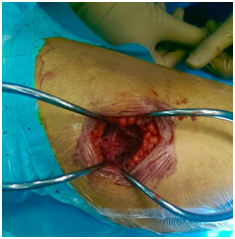

On an elective basis, we surgically removed the lesion followed by curettage and filling with a bone allograft via the lateral approach. The procedure was uncomplicated (Figure 3).

• Figure 3 Removal, curettage and insertion of bone allograft.